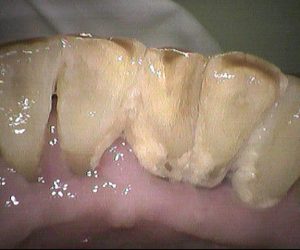

今日のクリーニングです。 クリーニング前 クリーニング後 3ヵ月毎にクリーニングにいらしている患者さんです。 下の前歯に歯石と磨き残しがありましたが しっかり除去して綺麗になりま […]